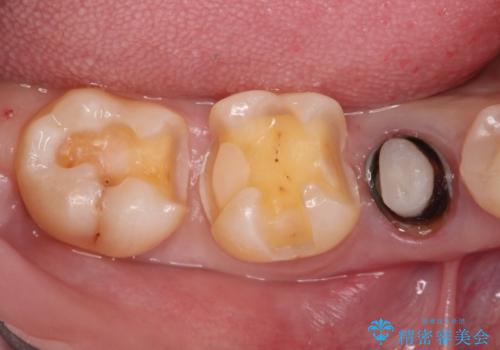

- 笑った時に見える金属を白くしたいとのことでメタルフリーの治療を希望され来院されました。

根管治療を行なったのち、オールセラミッククラウンにて修復処置を行っております。